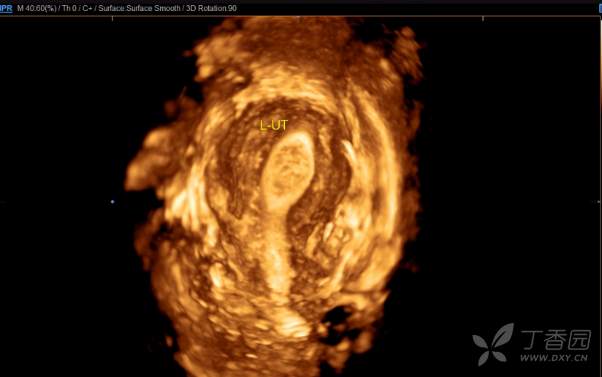

简要病史:此次患者来我院求医是因2020年12月右侧宫腔胚胎移植失败,生殖科考虑患者左侧宫腔条件比右侧宫腔要好,但多次宫腔镜未能探入左侧宫腔,B超提示左侧子宫内膜厚,回声不均(未见单),建议宫腔镜。阴道三维彩超:两个子宫大小分别为5.0×4.6×3.6cm(左侧 ),4.8×4.2×3.1cm(右侧 ),横切面宫底部为蝶状,宫体部横径增宽,可见两个宫腔内膜回声,左侧厚约1.0cm,回声不均匀,右侧厚约0.6cm,宫颈部呈哑铃状。复查彩超:双子宫,右侧宫腔内膜厚0.5cm,左侧宫腔内可见分离暗区,左侧子宫下段部分内膜中断,该处至宫颈外口长约4cm的范围内未见内膜回声。